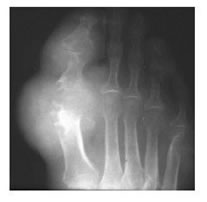

The #1 most common symptom of gout is extreme pain, swelling, throbbing and heat in the joint of your big toe.

Gout symptoms often begin in the big toe because blood flow is the lowest in the most distant extremities, particularly the toes. Gravity makes it more difficult for the body to carry the uric acid crystals away from that area.

- Arthritis attack that affects only one joint; most often affecting the toe, ankle, or knee. The first attack of gout most often affects the joints of the big toe. In fact, gout is thought to affect the big toe of 75% of all patients during the course of the disease.